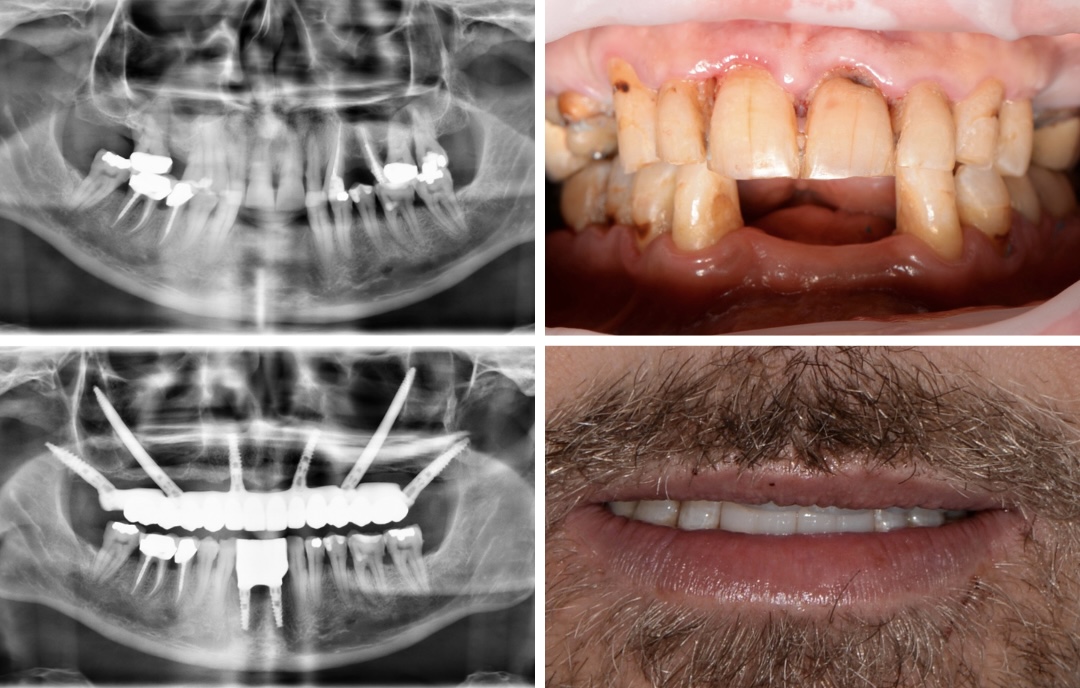

Ausgangssituation

Ein 63-jähriger Patient stellte sich mit einer ausgeprägten Atrophie im Ober- und Unterkiefer nach vollständigem Zahnverlust vor. Aufgrund des massiven Knochenabbaus bestand eine komplexe anatomische Ausgangslage, die eine konventionelle Implantatversorgung unmöglich machte. Der Fall war initial prothetisch und chirurgisch hoch anspruchsvoll.

Lösung

Die Behandlung erfolgte in einer Sitzung im Rahmen einer Full-Arch-Rekonstruktion mittels präziser digitaler Planung und dynamischer Navigation. Im Oberkiefer wurden inseriert:

- Zygoma-Implantate

- Transnasale Implantate

- Pterygoid-Implantate

Vorteile

- Maximale Nutzung des vorhandenen Restknochens

- Vermeidung umfangreicher Augmentationsverfahren

- Hohe chirurgische Präzision durch dynamische Navigation

- Sofortige funktionelle und ästhetische Rehabilitation

Vorhersagbares Behandlungsergebnis trotz komplexer Anatomie. Dieser Fall unterstreicht, dass moderne digitale Planung in Kombination mit navigationsgestützter Chirurgie selbst bei extremen Atrophien sichere und außergewöhnliche Ergebnisse ermöglichen kann.